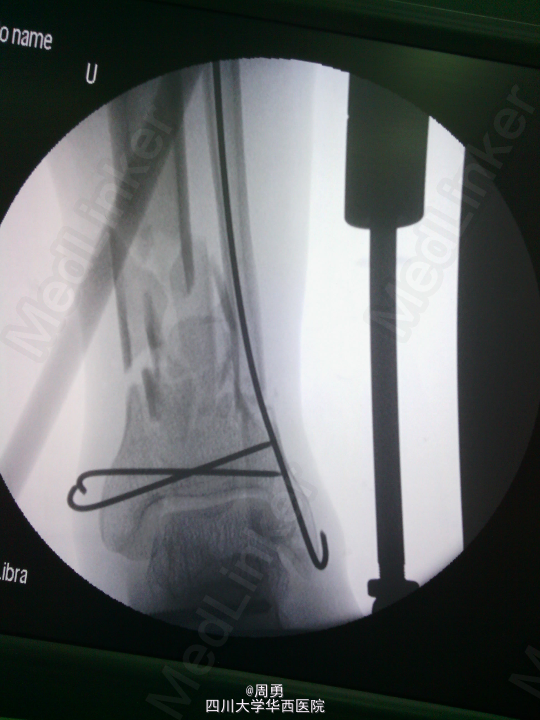

闭合穿针复位腓骨在开放性骨折中应用和意义

某些腓骨骨折常无需处理,但在开放性骨折一期处理创面同时,为了达到恢复肢体长度、条件允许情况下最大可能复位骨折、简化二期手术目的,某些时候复位腓骨并闭合穿克氏针对骨折复位和固定会有一定帮助,选几年前2个博士住院总期间X片示意,欢迎大家交流。